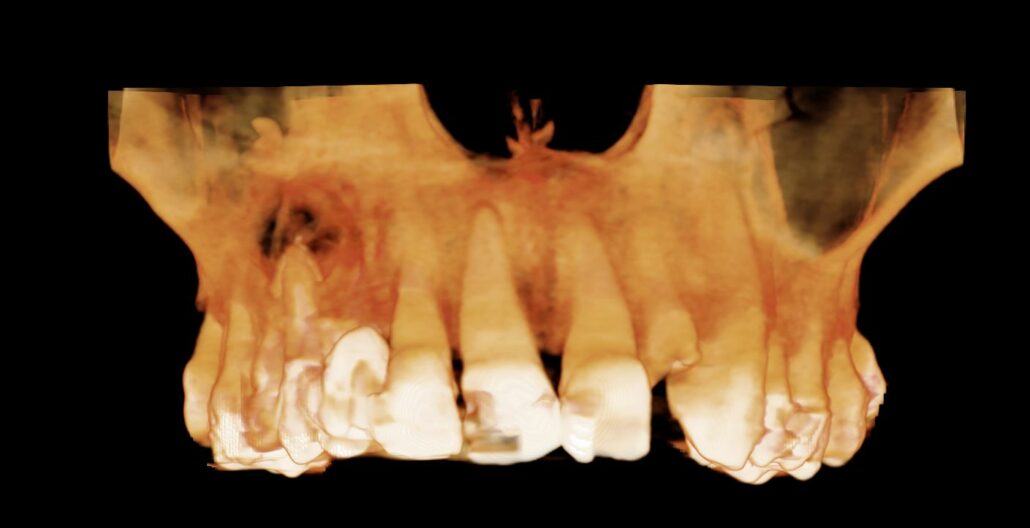

There is apical pathology on the UR6,5,4. The UR6 buccal roots have a large apical radiolucency. The UR4 and UR5 are root treated with large apical radiolucencies and destruction of the buccal cortical plate. These are probably apical granulomas or radicular cysts secondary to chronic apical periodontitis. They are contiguous and measure 12 x 25 x 9 mm.

Panoramic Reconstruction

Cropped panoramic and cross section of the alveolar ridge in the UR4-6 region showing chronic apical infection and reactionary bone formation in the right maxillary sinus